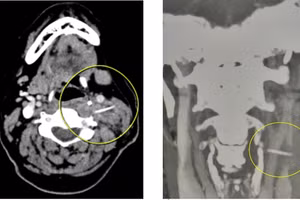

GD&TĐ - Ngày 16/3, Bệnh viện Đa khoa tỉnh Quảng Trị cho biết, vừa tiếp nhận điều trị cho một trường hợp bị hóc xương cá đâm vào lòng động mạch hiếm gặp.